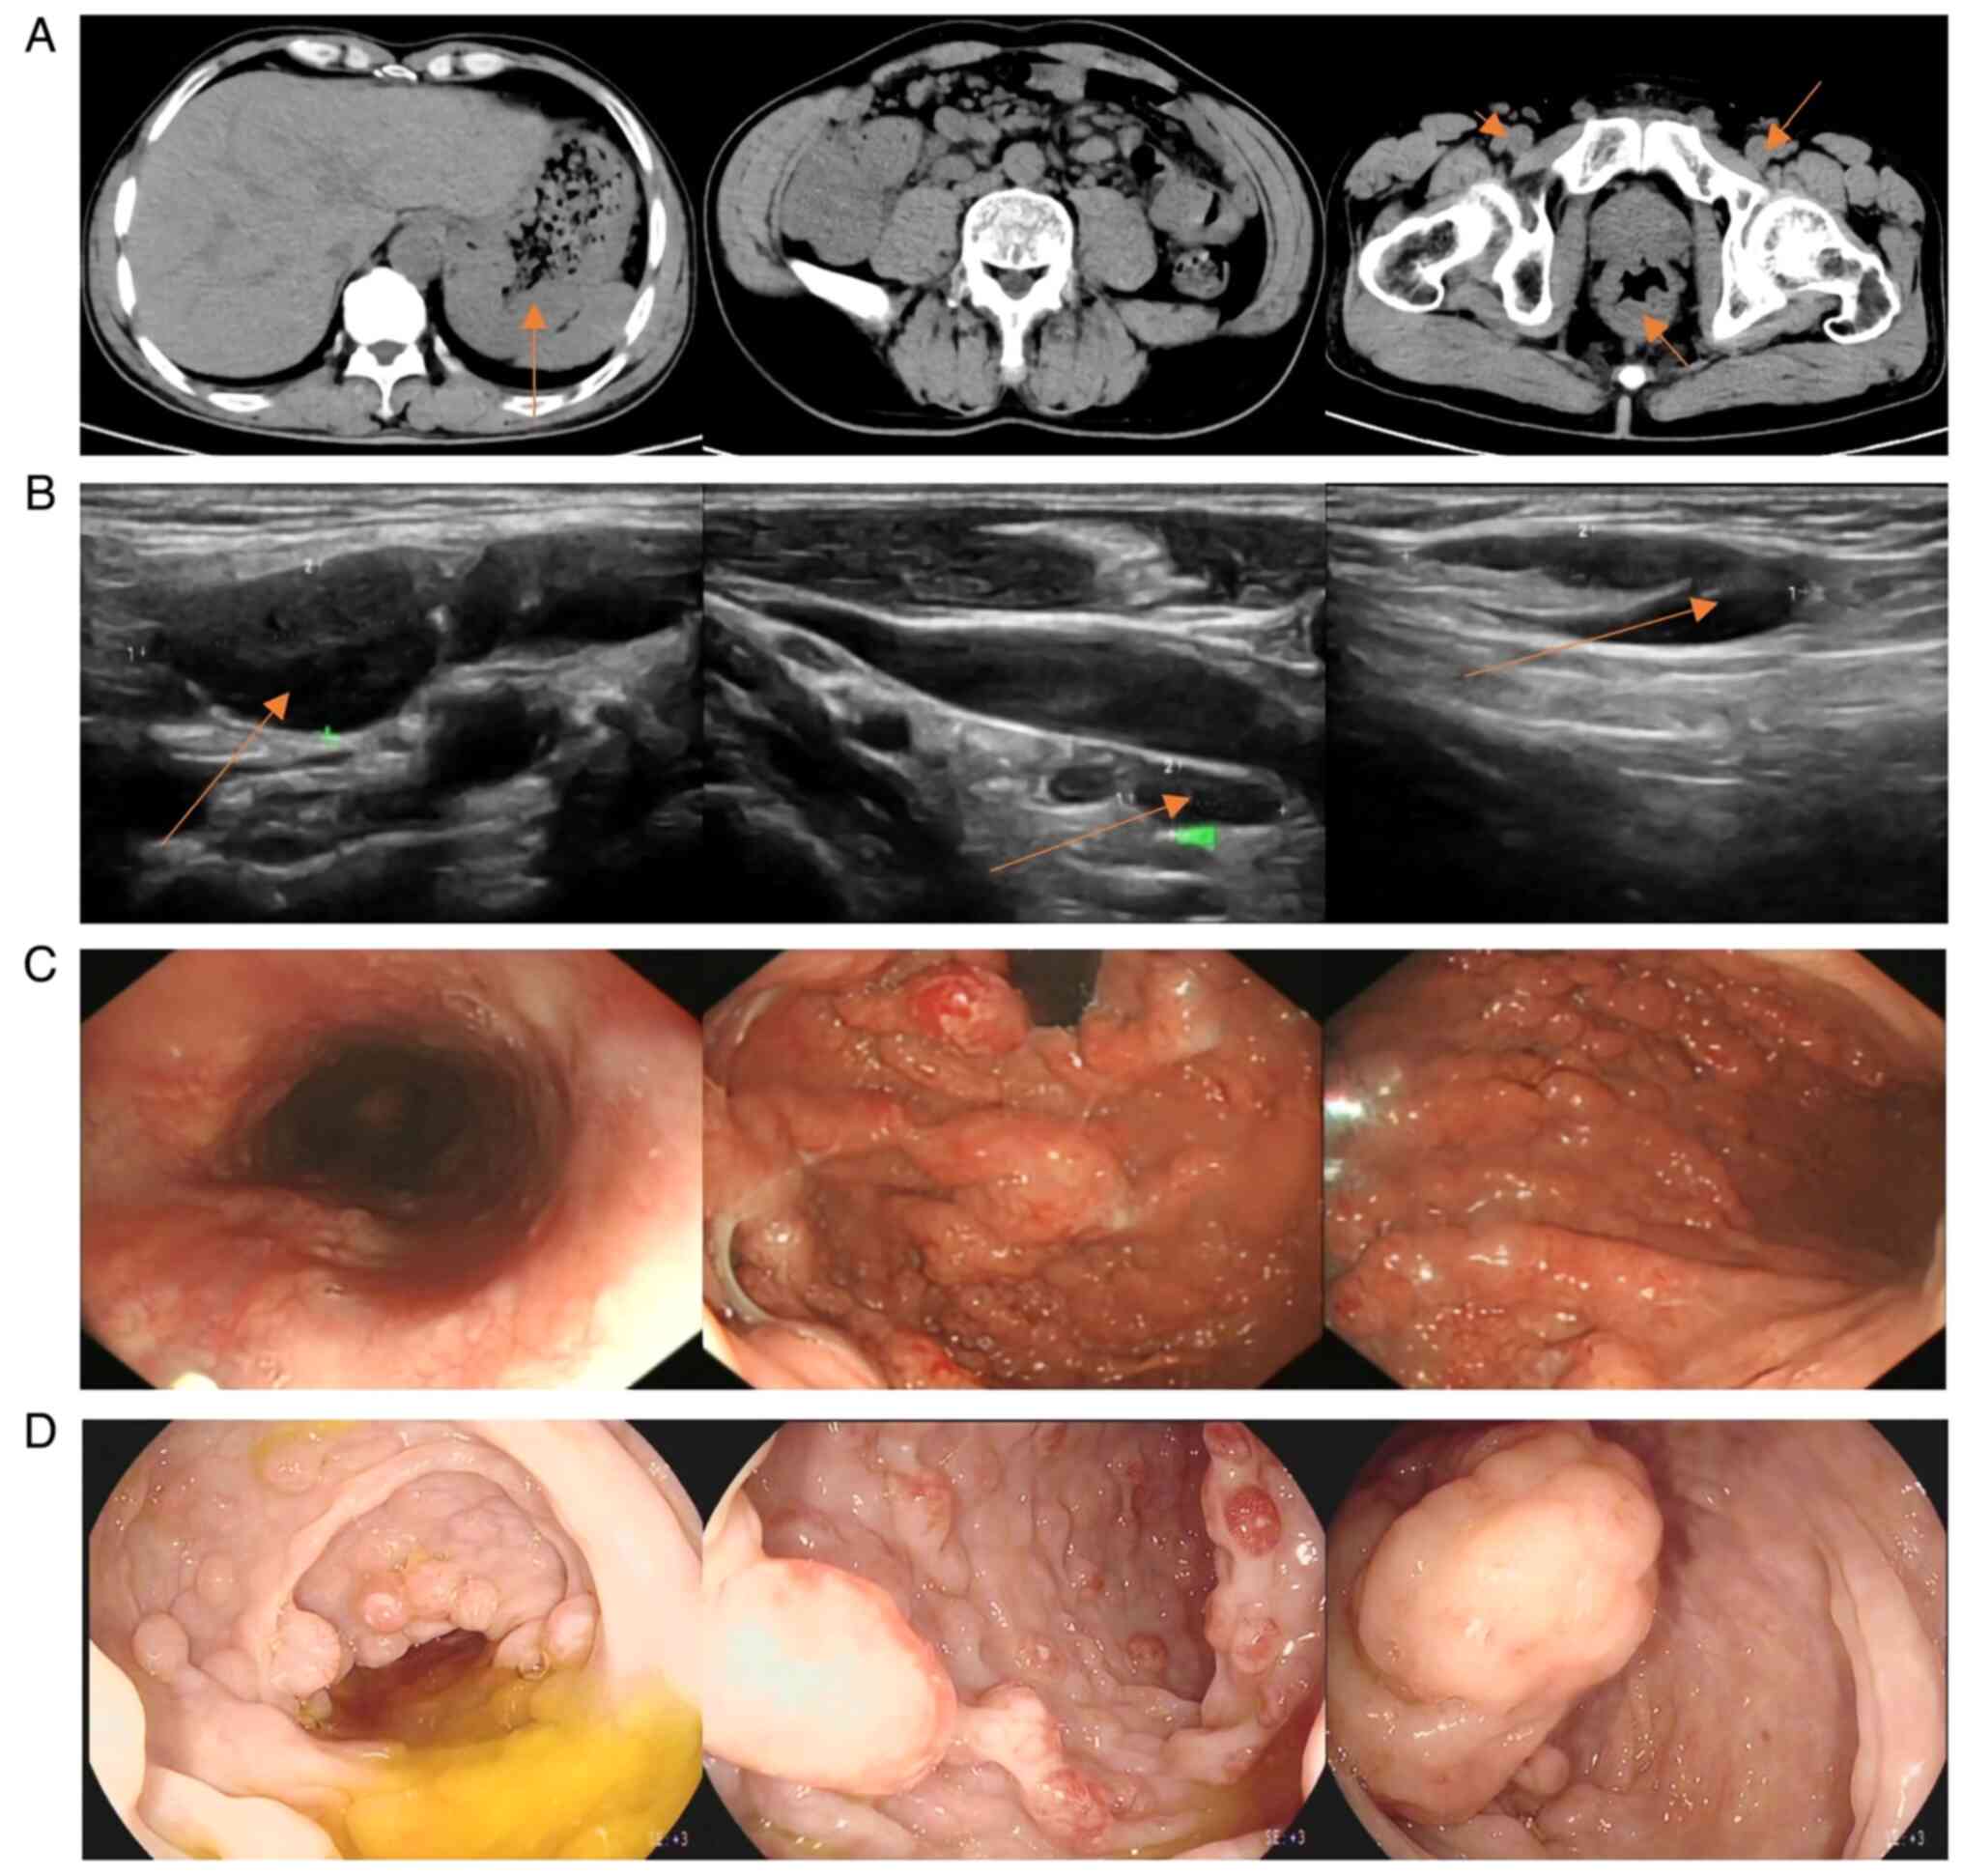

At admission, the body temperature of the patient was 36.4°C, the heart rate was 80 bpm and the blood pressure was 134/80 mmHg. Physical examination revealed mild tenderness of the upper abdomen and superficial lymph node enlargement in the neck, subclavian region and groin. Based on the clinical symptoms alone, the patient could easily be diagnosed with chronic gastritis. CT (Fig. 1A) showed multiple thickenings of the gastric and intestinal walls and numerous enlarged lymph nodes throughout the body. Superficial lymph node ultrasonography (Fig. 1B) revealed enlarged lymph nodes in the bilateral neck, upper and lower clavicle areas, armpits, groin and abdominal cavity. Gastroscopy (Fig. 1C) showed numerous wide basal and circular polypoid lesions in the entire gastric cavity, duodenal bulb and descending part, with rich vascular networks on the surface and a hard texture. Colonoscopy (Fig. 1D) revealed that the ileocecal valve was swollen and uneven, and the valve opening was not visible. The entire tract was covered with wide basal round or spindle-shaped polypoid lesions with a size of 0.5–1.5 cm. The surfaces of the polypoid lesions were rich in vascular networks, and a portion of the lesions were internally erosive, fragile and prone to bleeding. Other abnormal results included the fecal occult blood test [(+; normal value, (−); Colloidal Gold Method] and albumin level of 29.59 g/l (normal range, 35–55 g/l; Bromocresol Green Method). The white blood cell (WBC) count was 9.82×109/l (normal range, 4.00–10.00×109/l). The quantitative value of lactic dehydrogenase (LDH) was 205.4 U/l (normal range, 100.0–240.0 U/l). Based on the symptoms and examination results of the patient, lymphoma was suspected. Samples were fixed using 10% neutral buffered formalin at room temperature (20–26°C) for 24–48 h. Sections (3-µm thick) were stained with hematoxylin staining solution at room temperature for 1 min. The results (Fig. 2A and C); showed patchy lymphocyte infiltration in the mucosa, with local follicular structures. Fluorescence in situ hybridization (FISH; Fig. 2B) indicated that the lesion was CCND1/IGH (−), and immunohistochemical staining (Fig. 3) indicated that the lesion was CD21 (+), CD20 (+), Ki67 (+; 30%), Bcl-2 (+), Bcl-6 (mild+), CD5 (+), CyclinD1 (+) and SOX-11 (+). Therefore, the patient was diagnosed with MCL stage IV and scheduled to be transferred to the Department of Hematology of Hunan Provincial People's Hospital for chemotherapy. After completing tumor assessment, the patient received rituximab in combination with cyclophosphamide, doxorubicin, vincristine and prednisone chemotherapy (R-CHOP). After two cycles of R-CHOP (Table I), a CT scan (Fig. 4A) showed a marked reduction in lymph nodes in multiple areas and less thickening of the gastrointestinal wall compared with previous scans, but did not demonstrate complete response (CR) because there were still abnormalities. Treatment was changed to rituximab combined with etoposide, oxaliplatin and ifosfamide, with the addition of ibrutinib capsules (Table I). After completion of cycle 6 of the treatment, the patient underwent superficial lymph node ultrasonography, gastroscopy and positron emission tomography (PET)-CT in February 2024. The PET-CT scan (Fig. 4B) showed no significant hypermetabolic lesions in the gastrointestinal wall and the lymph nodes throughout the body. The superficial lymph node ultrasonography (Fig. 4C) did not reveal obvious lymph node enlargement. The gastroscopy (Fig. 4D) indicated that the polypoid lesions in the stomach had virtually disappeared. These results showed that the patient had achieved CR. The patient was followed up every 21 days with the medical record system of the hospital.

Figure 4.

(A) CT imaging demonstrating that the thickening of the gastric wall (arrow point), ileal wall and rectal wall was decreased compared with the previous state; and multiple enlarged lymph nodes were markedly reduced in size compared with their previous state (arrow point). (B) Positron emission tomography-CT demonstrating that no significant hypermetabolic foci were observed in the gastric wall, intestinal tract, spleen, nasopharynx, oropharynx and lymph nodes throughout the body, indicating that the activity of lymphoma was suppressed after treatment. (C) Superficial lymph node ultrasonography showed that the previously enlarged lymph nodes were reduced, including the left cervical lymph node (arrow point) size of 10×5 mm and the inguinal lymph node (arrow point) size of 8×3 mm. (D) Gastroscopy demonstrating that after the patient received rituximab in combination with chemotherapy, polypoid lesions were markedly reduced compared with before treatment.